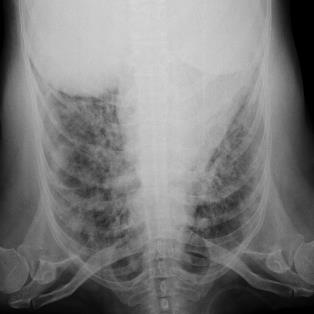

The COVID-19 disease was first discovered in Wuhan, China, and spread quickly worldwide. After the COVID-19 pandemic, many researchers have begun to identify a way to diagnose the COVID-19 using chest X-ray images. The early diagnosis of this disease can significantly impact the treatment process. In this article, we propose a new technique that is faster and more accurate than the other methods reported in the literature. The proposed method uses a combination of DenseNet169 and MobileNet Deep Neural Networks to extract the features of the patient's X-ray images. Using the univariate feature selection algorithm, we refined the features for the most important ones. Then we applied the selected features as input to the LightGBM (Light Gradient Boosting Machine) algorithm for classification. To assess the effectiveness of the proposed method, the ChestX-ray8 dataset, which includes 1125 X-ray images of the patient's chest, was used. The proposed method achieved 98.54% and 91.11% accuracies in the two-class (COVID-19, Healthy) and multi-class (COVID-19, Healthy, Pneumonia) classification problems, respectively. It is worth mentioning that we have used Gradient-weighted Class Activation Mapping (Grad-CAM) for further analysis.

翻译:COVID-19 疾病在中国武汉首次发现,并迅速蔓延到全世界。在COVID-19 流行病后,许多研究人员开始寻找一种方法,利用胸前X光图像诊断COVID-19 。早期诊断该疾病可以大大影响治疗过程。在本篇文章中,我们提出了一种比文献中报告的其他方法更快和更准确的新方法。拟议方法使用DenseNet169 和移动网络深神经网络的组合来提取病人X光图像的特征。在使用单向特征选择算法后,我们改进了最重要的特征。然后,我们将选定特征用作对光GBM(轻度推动机)算法的投入。为评估拟议方法的有效性,使用了ChestX-光8 数据集,其中包括病人胸部的1125 X光图像。拟议方法在两类(COVID-19,健康价值)和多级(COVID-19)中达到了98.54%和91.11%的缩略图。我们分别使用了“高度”的GRAMA-GRA级(C) 分别用于健康等级分析。